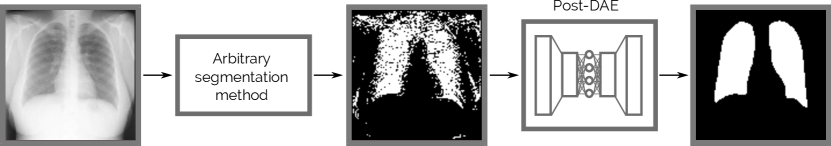

In this work we introduce Post-DAE, a post-processing method which improves pixel-level predictions generated with arbitrary classifiers by incorporating shape and topological priors. We employ denoising autoencoders (DAEs) to learn compact and non-linear representations of anatomical structures, using only segmentation masks. The DAE is then used to bring potentially erroneous segmentation masks into an anatomically plausible space (see Figure 1).

Refer to caption

Figure 1: Post-DAE worflow: the method is implemented as a post-processing step which maps arbitrary segmentation masks to anatomical plausible cases.